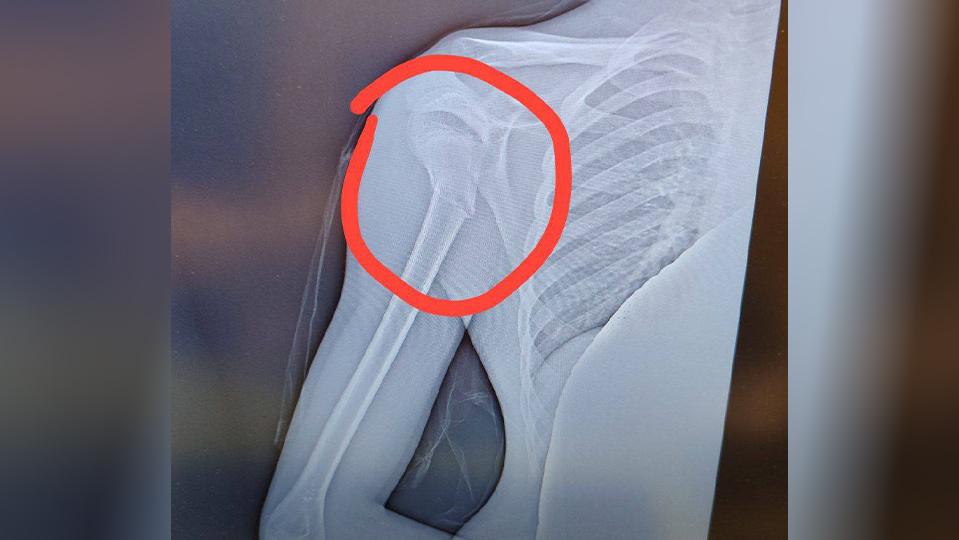

В результате у мальчика диагностировали перелом со смещением.

Как рассказали очевидцы, мужчина не впервые трогает детей. В этот раз нападавший ткнул мальчика лицом в снег, а после сделал подсечку, из-за чего мальчик сломал руку в районе плеча.